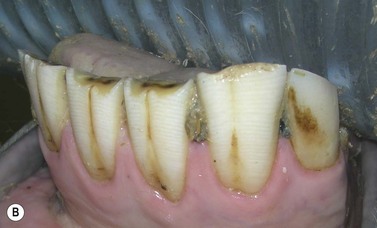

Fig. 8.17 This young horse has displaced and abnormally shaped maxillary incisors that additionally are suffering focal enamel caries – a rare feature at this site, that is likely caused by structural developmental defects.

image

Examples of dysplastic incisors (Figs 8.16 & 8.17) and dysplastic cheek teeth (Figs 8.14, 8.15, 8.18 & 8.19) are also presented here. Recent studies have shown dysplasia to be a relatively common finding in apically infected CT, and to predispose to the apical infection in a minority of cases, and two examples are shown here (Figs 8.20 & 8.21).2628 Some dysplastic teeth are of normal morphological structure and of normal shape but are excessively large i.e., macrodontia or too small, i.e., microdontia, and an example of the former is given in Figure 8.21.